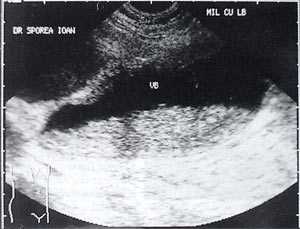

Рассматривая этиологию "желчного сладжа", его можно классифировать на вторичный и первичный. Вторичный сладж появляется, когда имеется хорошо известное этиопатогенетическое условие: после ударно-волновой литотрипсии по поводу желчных конкрементов, при желчно-каменной болезни, беременности [3, 4], циррозе печени, механической желтухе, водянке желчного пузыря, длительном парентеральном питании [5,6], сахарном диабете, серповидно-клеточной анемии [7], после приема цефтриаксона [8, 9]. Как первичный сладж расценивается в тех случаях, когда не может быть выявлено ни одно из указанных выше состояний.

Рис. 4. "Желчный сладж" у больного с циррозом печени.

Рис. 5. Желчный пузырь, заполненный сладжем, у больного циррозом.